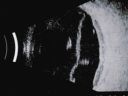

Choroidal Melanoma - Exudative Retinal Detachment 82 Year Old Man B Scan - Transverse1288 views82-year-old man who had 3 falls 2 weeks ago. After the falls he started checking his vision and noticed there was a veil over the left eye, which he had seen for about two weeks in the superior visual field. OD 20/25, OS 20/40

(patient was medically never well enough for brachytherapy and died 6 months later from heart disease)

Choroidal Melanoma - Exudative Retinal Detachment 82 Year Old Man B Scan Ultrasound Longitudinal1151 views82-year-old man who had 3 falls 2 weeks ago. After the falls he started checking his vision and noticed there was a veil over the left eye, which he had seen for about two weeks in the superior visual field. OD 20/25, OS 20/40

Choroidal Melanoma - Exudative Retinal Detachment 82 Year Old Man B Scan Ultrasound Transverce859 views82-year-old man who had 3 falls 2 weeks ago. After the falls he started checking his vision and noticed there was a veil over the left eye, which he had seen for about two weeks in the superior visual field. OD 20/25, OS 20/40